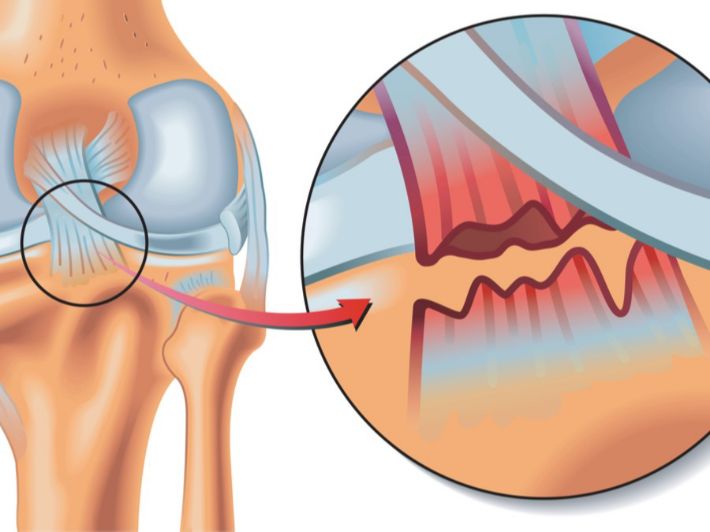

As mentioned earlier, hip fracture is a serious injury that occurs when the hip bones are broken. This type of injury often requires immediate medical attention, and the symptoms that may appear in the case of a hip fracture include:

Severe pain in the hip or lower back area, which may increase with movement or pressure on the affected area. Swelling and bruising may appear in the hip area due to the injury. The injured person may have difficulty moving or standing normally due to pain and damage to the hip area. There may be a change in the appearance of the affected area, such as ripples or changes in the texture of the skin. People with hip fractures may have difficulty urinating easily due to pain and pressure on internal organs. In some cases, blood may appear in the urine as a result of injury near the urinary organs.

Causes of Hip Fracture

There are some reasons that lead to hip fractures, including:

- Falling from a high place.

- Exposure to strong accidents and injuries.

- People with osteoporosis are more susceptible to fractures from simple movements or falling to the ground.

- Continuous pressure on the hip bones, such as during strenuous physical exercise.